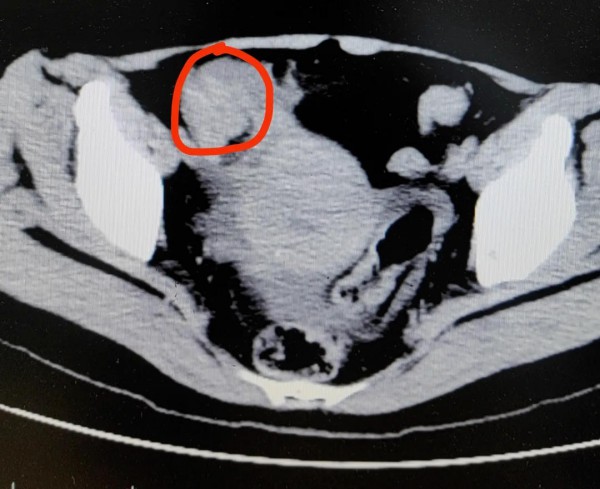

据杭州日报消息,一位患者冯女士(化名),在家一口气连吃3只柿子,晚餐又吃了2只大闸蟹。结果当天晚上,冯女士突然开始肚子痛,疼得全身冒冷汗,还不停呕吐。忍了两天后,冯女士终于忍无可忍,来到了医院。

医生高度怀疑,冯女士发生了绞窄性肠梗阻。最后手术从肠子里切出一堆“石头”,也就是俗称的“柿石症”,最大的直径有4公分!